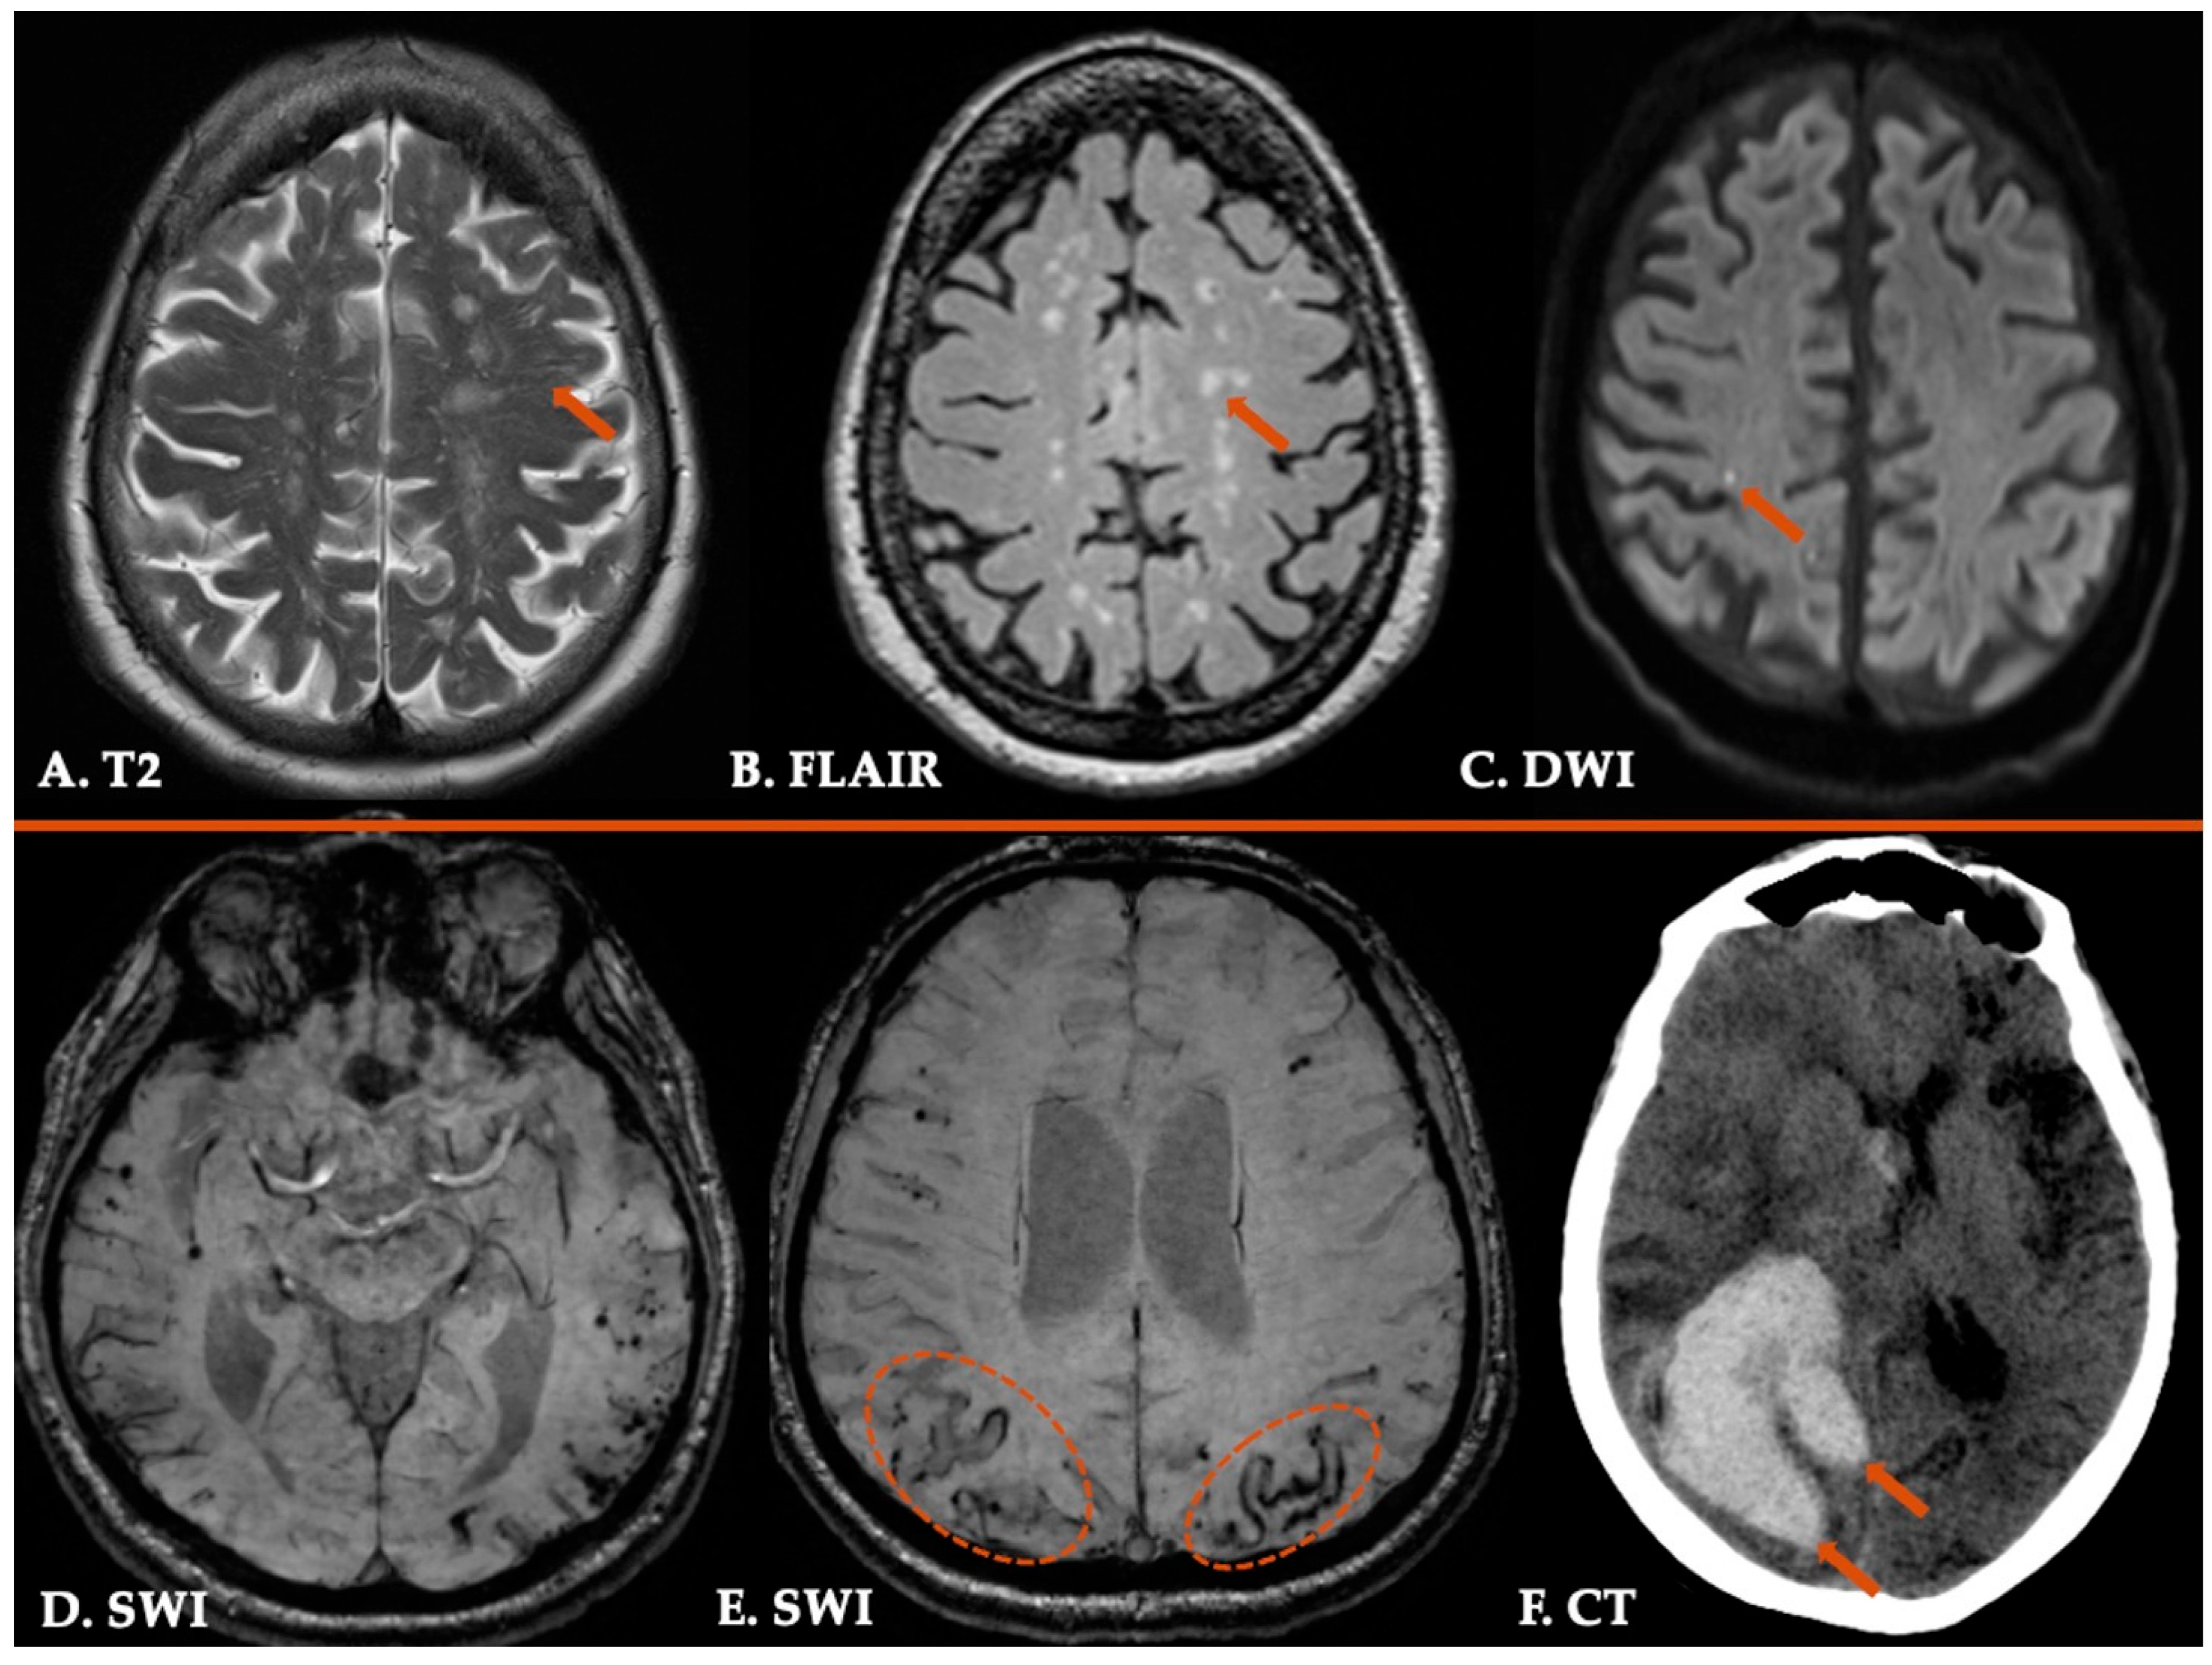

- Theodorou, A.; Tsibonakis, A.; Pateras, I.S.; Kaloudi, G.; Bakola, E.; Chondrogianni, M.; Andreadou, E.; Panayiotides, I.G.; Tsivgoulis, G. Multiple cerebral microinfarcts: An uncommon presentation of Cerebral Amyloid Angiopathy-related inflammation. Neurol. Res. Pract. 2023, 5, 28. [Google Scholar] [CrossRef]

- Theodorou, A.; Lachanis, S.; Alexopoulos, P.; Palaiodimou, L.; Kollia, N.; Voumvourakis, K.; Tsivgoulis, G. Teaching NeuroImages: Acute convexity subarachnoid hemorrhage: An underrecognized presentation of CAA-ri. Neurology 2019, 93, e524–e525. [Google Scholar] [CrossRef] [PubMed]

| 2. Probable CAA-ri | 1. Age > 40 y 2. Presence of ≥1 of the following clinical features: headache, decrease in consciousness, behavioral change, or focal neurological signs and seizures; the presentation is not directly attributable to an acute ICH 3. MRI shows unifocal or multifocal WMH lesions (corticosubcortical or deep) that are asymmetric and extend to the immediately subcortical white matter; the asymmetry is not due to past ICH 4. Presence of ≥1 of the following corticosubcortical hemorrhagic lesions: cerebral macrobleed, cerebral microbleed, or cortical superficial siderosis 5. Absence of neoplastic, infectious, or other cause |

| 3. Possible CAA-ri | 1. Age ≥ 40 y 2. Presence of ≥1 of the following clinical features: headache, decrease in consciousness, behavioral change, or focal neurological signs and seizures; the presentation is not directly attributable to an acute ICH 3. MRI shows WMH lesions that extend to the immediately subcortical white matter 4. Presence of ≥1 of the following corticosubcortical hemorrhagic lesions: cerebral macrobleed, cerebral microbleed, or cortical superficial siderosis 5. Absence of neoplastic, infectious, or other cause |